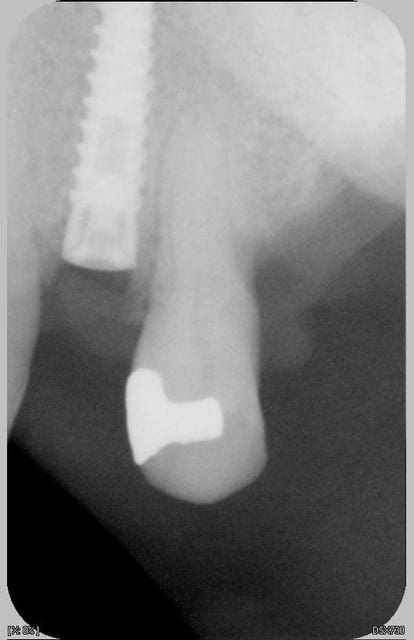

Non Annie, l'implant ne rentre pas dans la racine de 25. L'espace est étroit, mais l'implant est bien centré (voir Rx jointe).

En ce qui concerne les antagonistes, la 37 est + solide qu'il n'y parait à la Rx malgré une petite perte osseuse mésiale. J'ai réalisé un bridge 35/36/37 pendant l'ostéointégration. (l'effondrement de la crête ne permettant pas la pose d’un implant/36).

pourquoi ne pas avoir mis 3 implants en 46_47 ou les avoir plus écarté pour éviter le porte à faux distal engendrant un risque biomécanique ? crête trop étroite ?